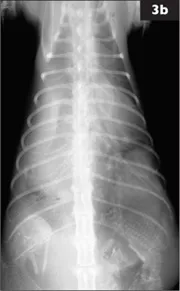

3 A 3-year-old female DSH cat is presented for 1 week of lethargy and increased respiratory effort. She is at 56 days of gestation. A similar episode occurred with the previous pregnancy and responded favorably to antibiotic therapy. This episode seems to be worse. Right lateral (3a) and DV (3b) thoracic radiographs are made.

i. What radiographic abnormalities are evident?

ii. What is the radiographic diagnosis?

3 i. There is increased opacity in the ventral and right halves of the thoracic cavity. Only a short dorsal segment of the left crus of the diaphragm is distinct; the remainder is effaced by the increased thoracic opacity. The trachea is displaced dorsally, but remains mid-line in the DV view. The heart is shifted dorsally and to the left. Only the left lung lobes are well inflated with well-defined vessels. The increased thoracic opacity is a mix of solid soft tissue or fluid and mineralized opacity of fetal skeletal structures. A fetal skull is evident ventrally at the 5th intercostal space and a different fetal lumbar spine crosses the pleura-peritoneal junction ventrally.

ii. Right-sided diaphragmatic hernia with thoracic displacement of gravid uterus and probably liver. The degree of fetal skeletal mineralization is consistent with late-term gestation. No signs of fetal death are evident. Ultrasound would be valuable to determine fetal viability. In several reports, the most common organs to be herniated through a tear in the diaphragm are liver, stomach, and small intestine. Several case reports of diaphragmatic herniation of gravid uterus in dogs appear in the literature.